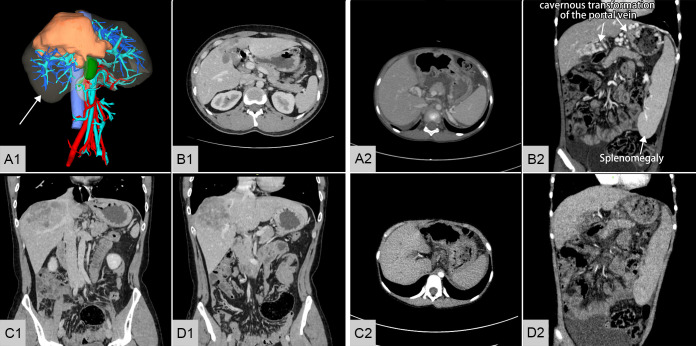

Heterotopic Auxiliary Liver Transplantation in a Child with Portal Hypertension Using a Discarded Partial Right Liver Allograft from an Adult Patient with Alveolar Echinococcosis.

异位辅助性肝移植治疗门脉高压症患儿使用成人肺泡包虫病患者丢弃的部分右同种异体肝。